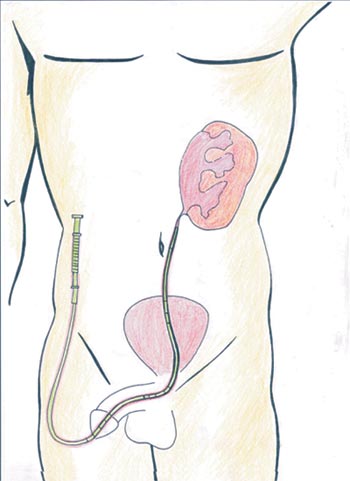

With the patient in lithotomic position, a cystoscopy is performed with the accomplishment of a retrograde ureteropyeloghaphy (Photo 1). Afterwards, a 7 F ureteral catheter is inserted with one tip placed bellow the ureteropelvic junction and the other outside the urethra connected to an 8 F Levine catheter. (Figure1).

Figure 1 - Diagrammatic representation of the exact position of the catheter over the UPJ and the other distal tip outside the urethra.

Transperitoneal access was used; however, retroperitoneal access is also feasible. The intra-ureteral catheter facilitates its identification (Figure 2 and Photo 3). The ureter is traced cephalad toward the renal pelvis. NS (normal saline) 0,9% can also be injected through Levine catheter to distend even more the renal pelvis facilitating its identification (Figure 3 and 4). A 3.0 long straight needle could be passed percutaneously or not to lift the pelvis and therefore saving a trocar (Photo 4).

Figure 2 - Diagrammatic representation of the ureteral catheter increasing the ureter consistency.